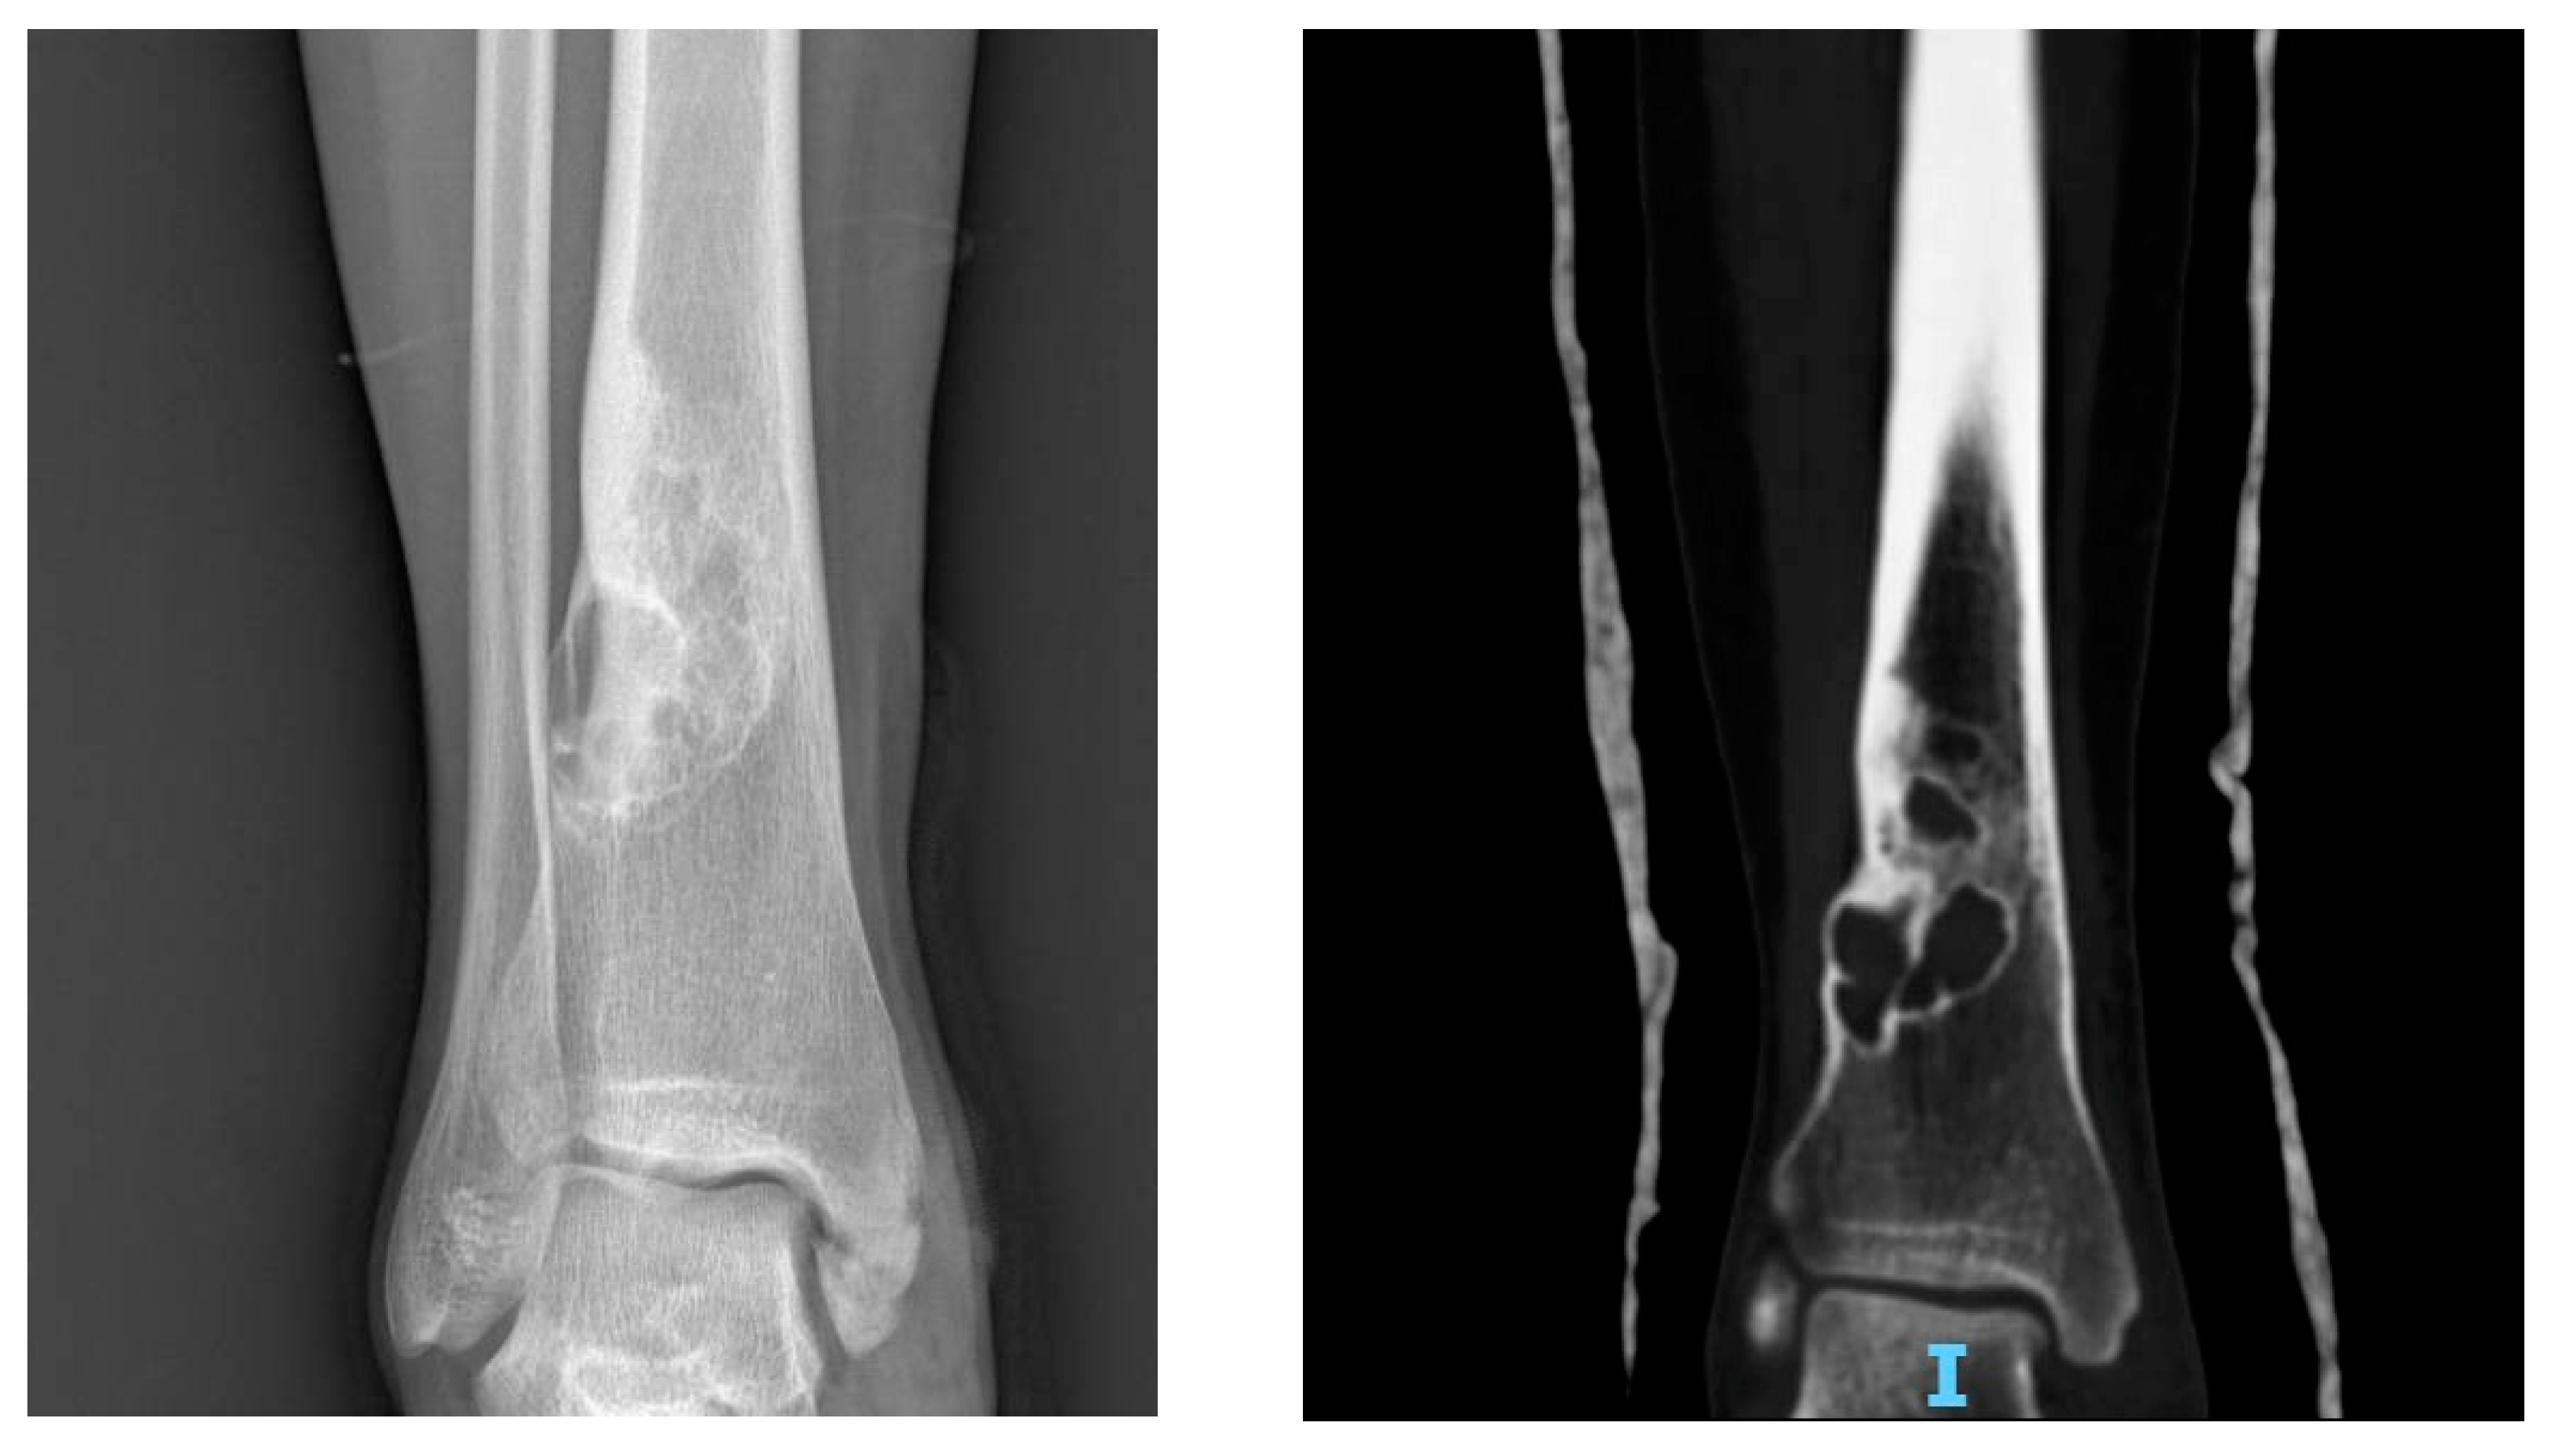

3.1.5. Imaging

At X-ray examination, osteochondroma is usually localized in the metaphysis, and its cortex is in continuity through a marrow cavity with the originating bone cortex. In the case of symptomatic patients, further investigations could be necessary with MRI, CT, or US. MRI is helpful to evaluate the cartilage cap and bone thickness in adults and the possible complications, such as bursae, neurological, and vascular involvement [59]. Scintigraphy shows enhancement in benign and malignant lesions; for this reason, it is not a valuable test for diagnostic purposes (Figure 2).

Figure 2.

X-rays of multiple osteochondromas.